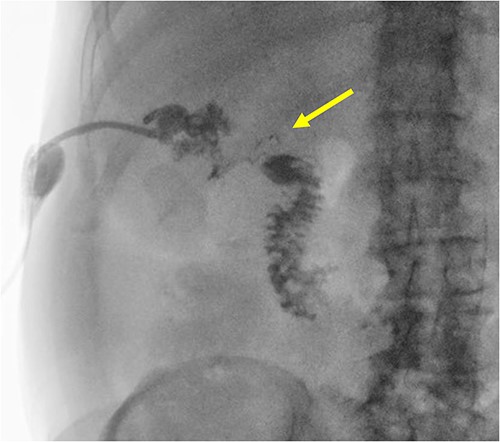

The patient is a 63-year-old male who underwent laparoscopic cholecystectomy with intraoperative cholangiogram for symptomatic gallstone disease at an outside hospital 2 years prior to our initial visit. His postoperative course was complicated by biloma and retained gallstones in the common bile duct, for which he underwent endoscopic biliary sphincterotomy 4 months after the initial surgery. His medical history was notable for alcoholic cirrhosis with a Model for End-Stage Liver Disease score of 14, duodenal ulcers, and gastric angiodysplasia. Symptoms included intermittent abdominal discomfort, nausea, and vomiting 1 year after the cholecystectomy. Computed tomography (CT) showed a perihepatic abscess measuring up to 7.5 × 5.1 cm, containing gallstones and punctate free-air near the right hepatic lobe (Fig. 1). He underwent image-guided percutaneous drainage of the hepatic abscess. A fistulogram via the abdominal drain demonstrated communication between the abscess cavity and the second segment of the duodenum, confirming the presence of a duodenal-perihepatic fistula, feeding the abscess cavity (Fig. 2). Interestingly, the oral contrast administered during a prior abdominal CT scan did not demonstrate this fistulous connection. The patient underwent endoscopic closure of the fistula using an over-the-scope clip device (Fig. 3). Repeat CT 2 months following the closure showed that the perihepatic abscess decreased in size with no evidence of a new abscess. On initial follow-up, the patient demonstrated clinical improvement in his overall health. Continued follow up revealed near complete resolution of the perihepatic abscesses and continued clinical improvement.

CT in the transverse plane demonstrating a perihepatic gallstone-containing collection of fluid measuring up to 7.5 × 5.1 cm.